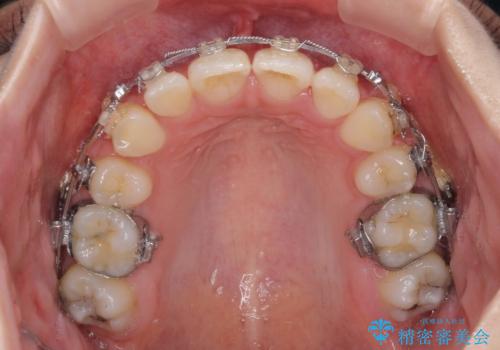

治療途中で転院 抜歯矯正の仕上げ治療

- 地元で抜歯治療を行っている途中、東京へ転職したため治療を継続して欲しいとのことで来院された患者様です。

出っ歯を抜歯矯正にて治療をしていらっしゃいましたが、抜歯スペースが少し残っていたため、閉じて歯列を仕上げていくこととしました。